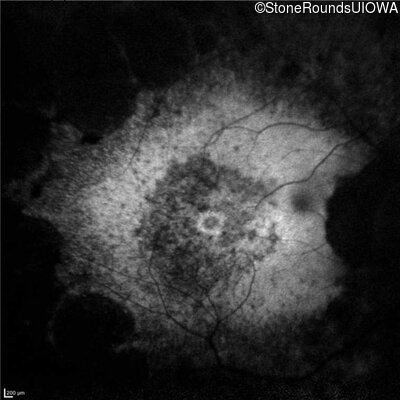

Age at visit: 59 years

This 59 year old woman has been night blind for as long as she can remember. She first noted constricted visual fields in her late 30s.